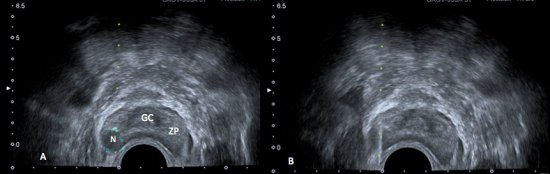

A ultrassonografia transretal, realizada através de transdutores endocavitários, permite uma melhor definição da anatomia prostática, diferenciando a zona periférica, que é hiperecogênica, das zonas central e de transição, que são hipoecogênicas.4

Cerca de 60 – 70% dos tumores da zona periférica são hipoecogênicos em relação ao restante da próstata (fig. 1), entretanto apenas 17 – 57% dos focos hipoecogênicos representam câncer. Causas benignas como atrofia ou prostatite se apresentam de forma semelhante no ultrassom transretal. Além disso, 30 a 40% dos tumores são isoecogênicos, indistinguíveis do parênquima prostático normal. A USTR em pacientes sem alterações ao toque retal apresenta sensibilidade de apenas 30-45%.7,8

Figura 1. A) Ultrassonografia transretal da próstata demonstrando a anatomia prostática: glândula central (GC) discretamente hipoecogênica, e a zona periférica (ZP), mais ecogênica. Nota-se nódulo (N) bem delimitado, hipoecogênico, na zona periférica. B) Biópsia transretal da próstata.